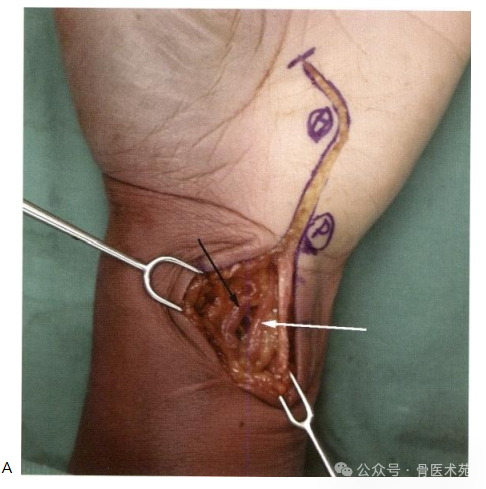

尺神经和尺动脉于切口近端易于辨认,位于尺侧腕屈肌肌腱的桡侧(图3.4)。切 开所有浅层组织后,易于向远侧探查。皮下脂肪应钝性分离,以避免皮神经损伤。掌 短肌可稍向尺侧牵开,腕掌侧韧带和豆钩韧带可切断,以完整减压腕尺侧管。在豌豆 骨水平可辨明尺神经的两个分支。

图3.4 (A,B) 尺动脉(白箭头)和尺神经(黑箭头)可于尺侧腕屈肌肌腱的桡侧识别